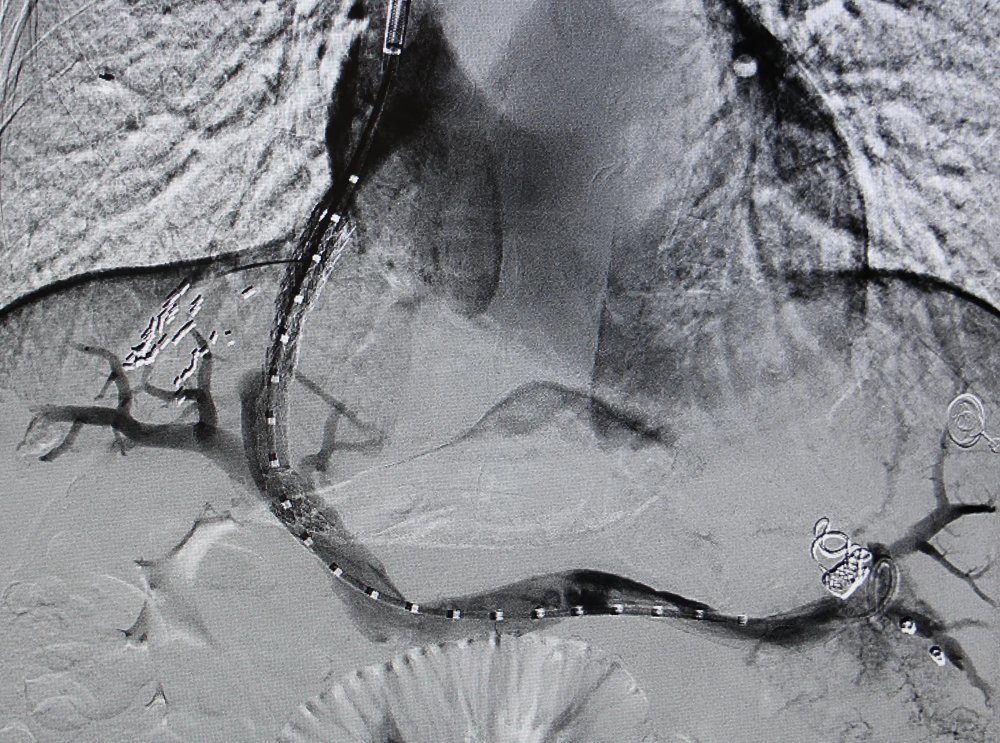

5月15日,手术按计划进行,在卜高峰及其团队的配合下,张明主任首先经颈静脉穿刺,引入导管至肝静脉,随后在DSA影像引导下精准穿刺肝内门静脉分支,建立肝静脉-门静脉通路。导丝通过后,球囊扩张分流道,并成功植入覆膜支架,用一根导丝,在患者肝脏内架起了一座生命“立交桥”,整个手术历时不到1小时。术中患者处于清醒状态,无明显不适,术后患者门静脉压力显著下降,生命体征平稳。